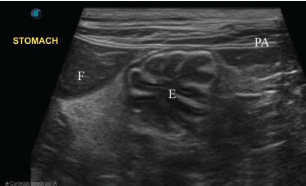

The stomach is ultrasounded caudally to the liver, close to the xiphoid process, slightly to the right (Larson and Biller, 2009). The stomach is identified by its size, regular peristalsis (four to five contractions per minute), and folds in the wall that, when empty, create a characteristic “wagon wheel” appearance (Penninck et al., 1990). The gastric wall has five distinct layers: mucosa, submucosa, muscularis, serosa, and luminal surface (König and Liebich, 2021). The mucosa and muscularis are hypoechogenic, whereas the other layers are hyperechogenic (Fig. 1) (Penninck et al., 1990; Burk and Ackerman, 1996). To measure gastric thickness, it is important to avoid folds in the stomach, which can cause a false impression of enlargement due to contractions or image artifacts, and the measurement is no more than 0.29 cm (Fig. 2) (Irom et al., 2014; Griffin, 2019). Assessment includes the analysis of thickness, stratification of layers, peristaltic activity, intraluminal content, and perigastric structures, such as lymph nodes, omentum, and the presence of gas or free fluid (Larson and Biller, 2009).

Fig. 1. Ultrasound (linear transducer, 8 MHz) of the stomach of an adult cat in a cross-section. Stomach (S) with the appearance of a wagon wheel, liver (L) cranial to the stomach, and abdominal wall (AW) ventral to the stomach. Source: Personal archive, 2025.